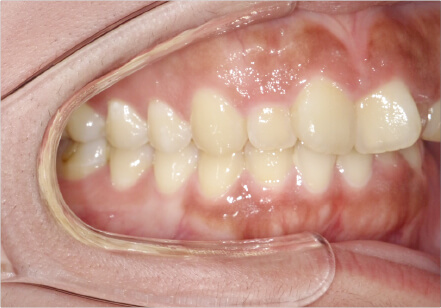

叢生の症例

17歳

女性

相談内容

カウンセリング・診断結果

治療内容・方法

全額アライナー矯正

術後の経過・現在の様子

クリアライナー使用

治療のリスク

痛み・歯根吸収・歯肉退縮・虫歯・後戻り

費用・治療期間

715,000円、2年10ヶ月